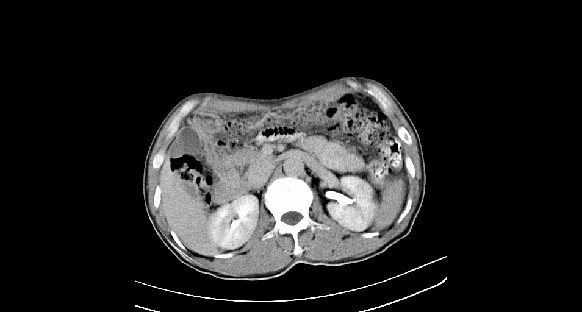

男性,70岁,体检b超发现左肾占位,请各位战友发表一下观点

左肾有两个病灶,且较大的病灶内可见点状钙化灶,增强扫描边缘也是呈渐进性强化,中央部分未见明显强化